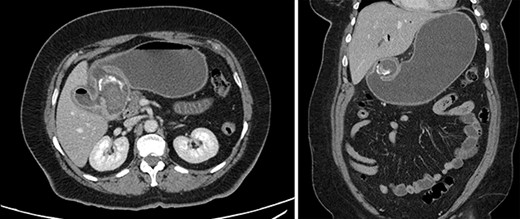

The patient was afebrile and hemodynamically stable. Physical exam revealed a soft, non-tender abdomen with no distension and no palpable masses. Labs were significant for hyponatremia (130 mmol/L) and leukocytosis (11.6 k/μL). Liver panel was unremarkable. CT of the abdomen with intravenous (IV) contrast demonstrated a 2.6 cm stone in the proximal duodenum, gallbladder wall thickening, fat stranding in the porta hepatis and pneumobilia (Fig. 1).

Contrast-enhanced computed tomography (CT). Axial and coronal views of a 2.6 cm stone in the proximal duodenum, gallbladder wall thickening, fat stranding in the porta hepatis and pneumobilia in the non-operative patient.